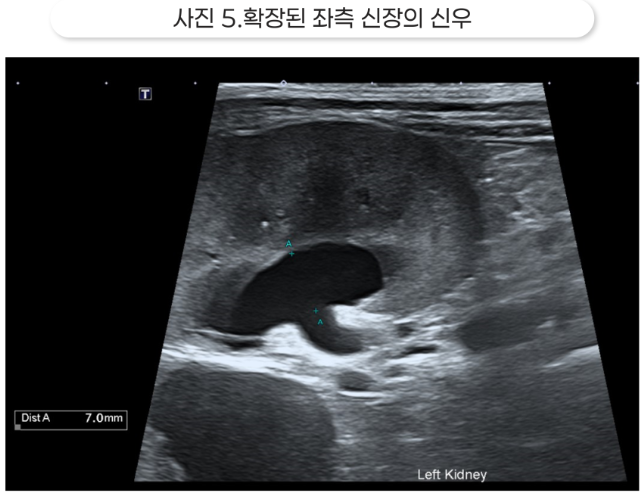

초음파 영상에서는 양측 수신증과 요관 결석이 확인되었습니다.

결석보다 가까운 쪽의 요관은 확장되어 있는데, 이는 요관 폐색을 의미합니다. 신우가 매우 확장되어 있었고, 특히 오른쪽 신장은 피질이 많이 얇아져 있고 심한 수신증 소견을 보였습니다.

수신증이 너무 심하면 해당 신장은 이미 기능을 상실했을 가능성이 높습니다.